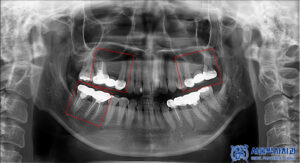

파노라마 촬영으로

전체 상태를 먼저 확인했습니다.

다만 크라운은 방사선 불투과성이 있어

내부 평가가 제한되므로,

정밀 엑스레이를 추가로 촬영해

보철물 하방 상태를 점검했습니다.

그 결과, 브릿지 아래쪽에

우식이 진행된 것이 확인되었습니다.